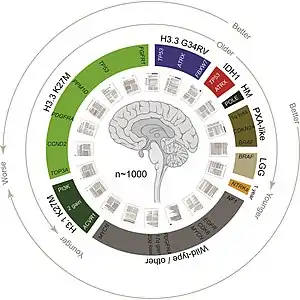

The definitive genetic marker of a diffuse midline glioma is H3K27me3 loss. Diffuse midline gliomas have three known subtypes:[23]